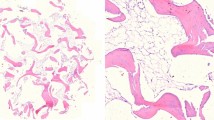

The cartilage samples were fixed in 4% formaldehyde for at least 2 days. After fixation, two representative sections from each sample were cut. Then, the tissues were dehydrated and embedded in paraffin according to the standard histopathological processing and 4-μm-thick sections were cut by microtome. The slides were stained with hematoxylin–eosin.

It is important to note that most of the classifications found in the literature are applied only for degenerative conditions, not for trauma cases. In the case of healthy, control hyaline cartilage samples, histological examination confirmed the absence of pathologic findings (Fig. 3a).